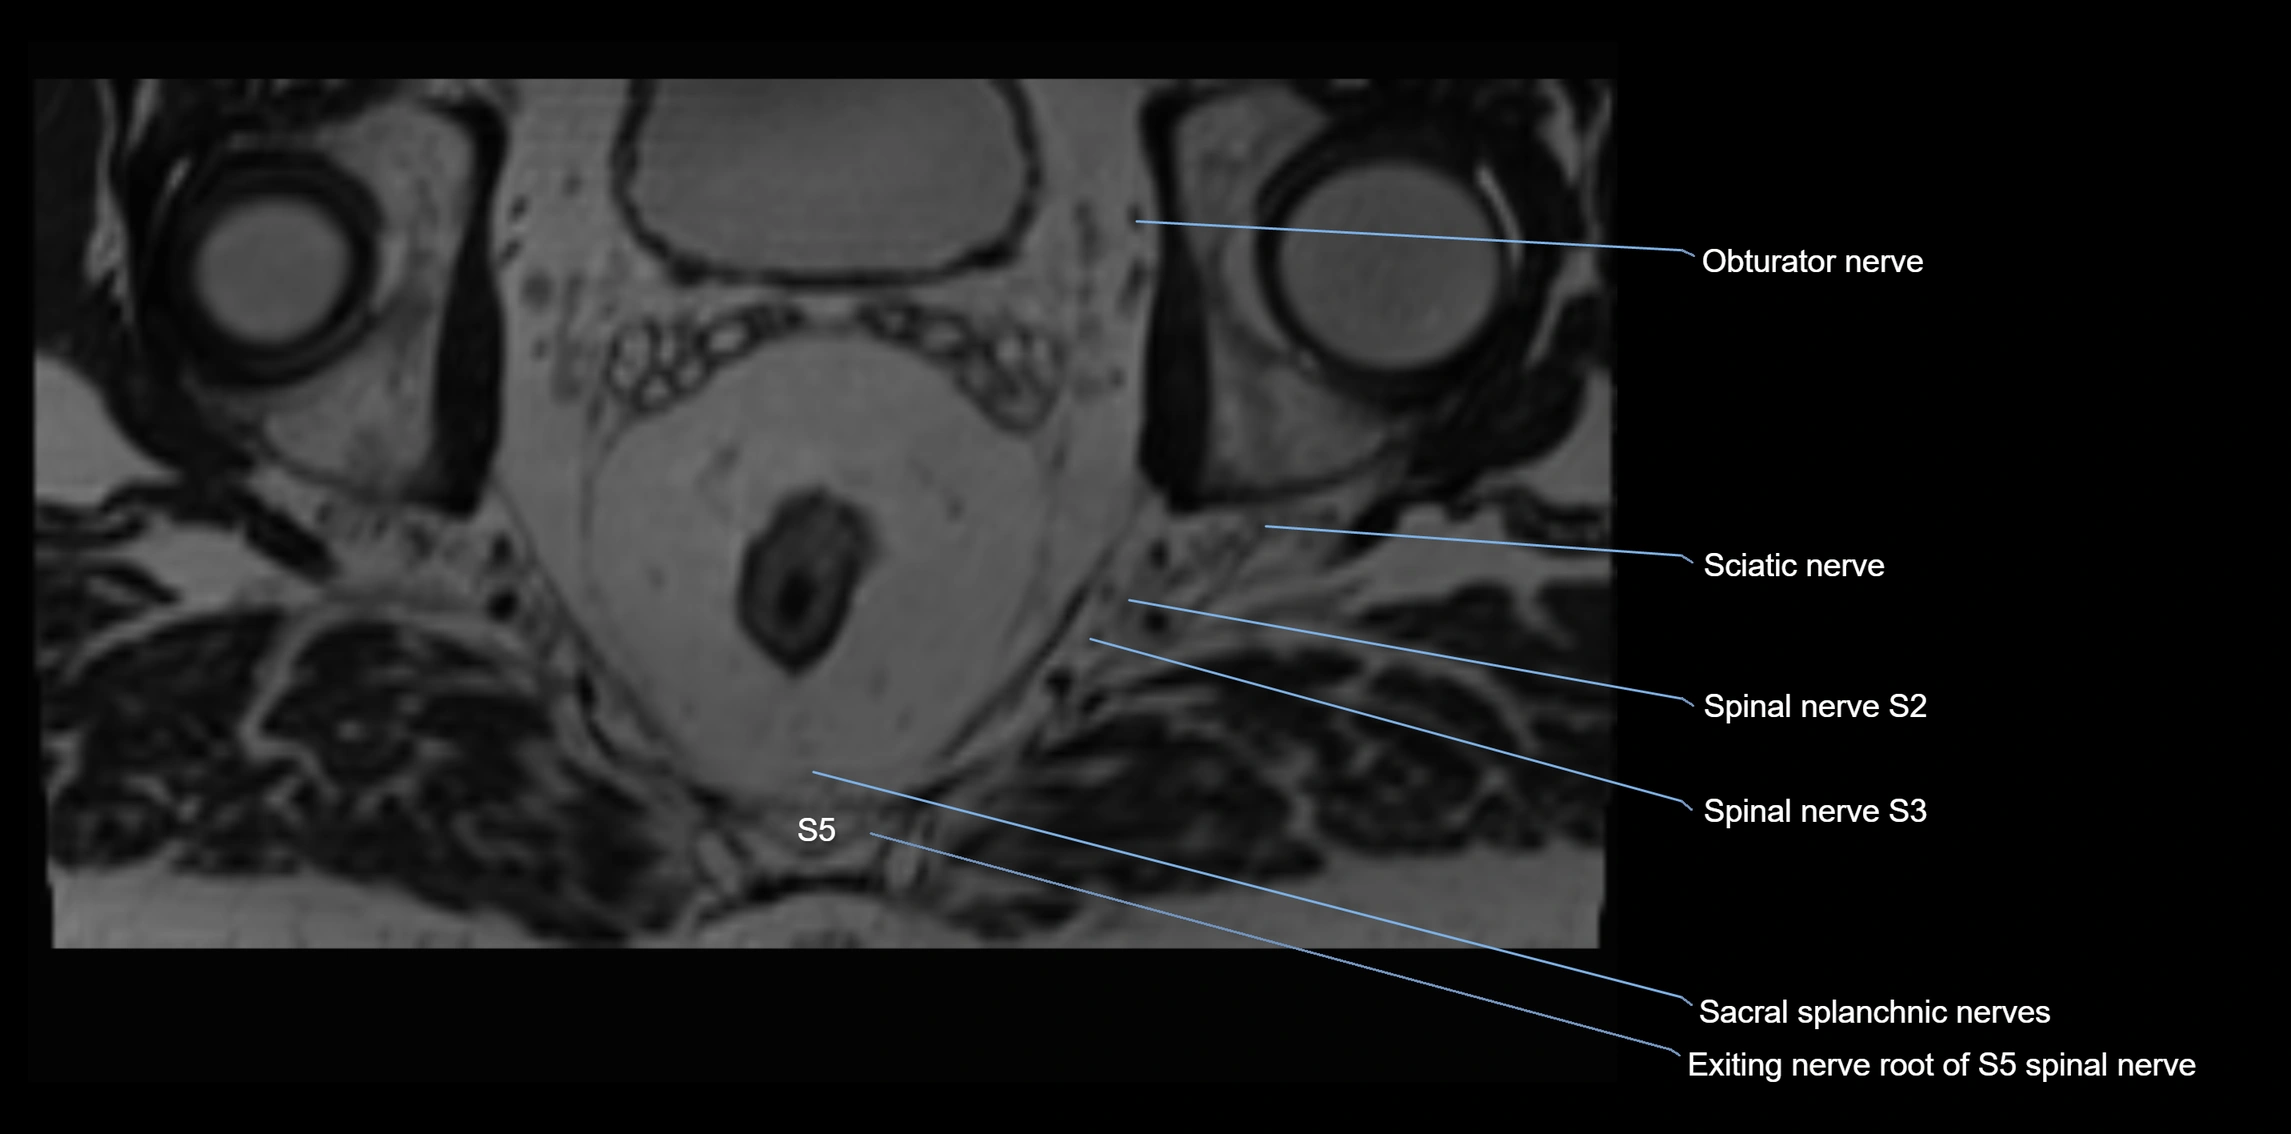

MRI image

image